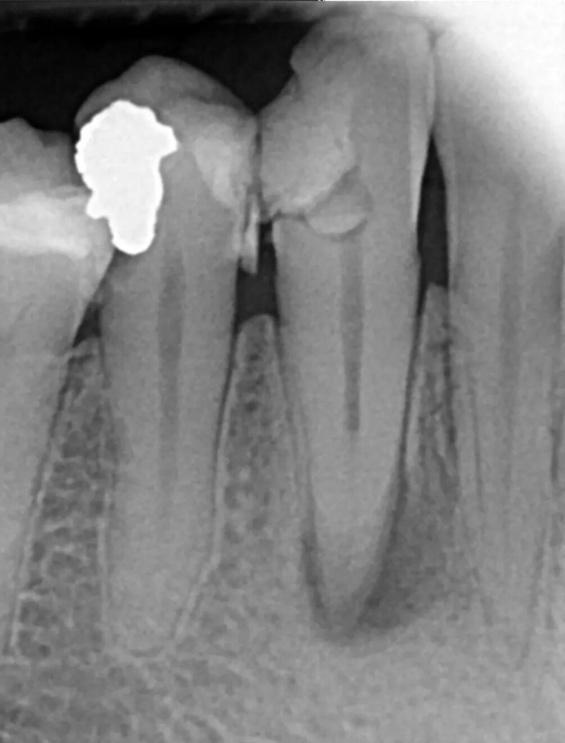

A-35-year-old female was referred for root canal treatment of the right mandibular canine. The general dental practitioner had started root canal treatment. The tooth was asymptomatic and free from any clinical signs. Medical history was unremarkable.

Clinical examination revealed no mobility, normal periodontium, no swelling or sinus tract, and the tooth was not tender to percussion. Pulp sensitivity testing of the tooth showed no response to cold and electrical pulp testing. Radiographic evaluation of the affected tooth revealed unusual, complex root canal anatomy. The radiographic image showed the presence of two roots with periapical radiolucency (Fig. 3).

Based on history, clinical examination, a diagnosis of necrotic pulp and apical periodontitis was established for lower right canine (#43). Root canal treatment was decided, and informed consent was taken from the patient.